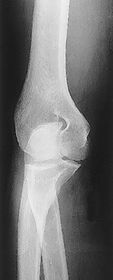

A. radial and coronoid fossas B. capitulum C. trochlea D. coronoid process E. radial tuberosity F. radial neck G. radial head H. trochlear sulcus I. trochlear notch J. olecranon process K. epicondyle L. olecranon fossa

G. superimposed epicondyles of humerus I. trochlear sulcus J. trochlear notch K. outer ridges of capitulum and trochlea L. coronoid process of ulna M. radial head N. radial neck

a. outer ridges of capitulum and trochlea b. trochlear notch c. trochlear sulcus

1. trochlear sulcus 2. outer ridges of capitulum and trochlea 3. trochlear notch